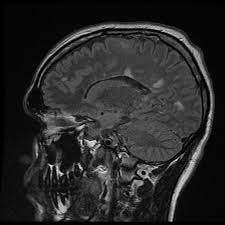

Widespread use of mri (magnetic resonance imaging) has revolutionized the ability to diagnose multiple sclerosis. Optic nerve evaluation within normal limits. Magnetic resonance imaging (mri) plays a crucial role in multiple sclerosis (ms) diagnosis, disease monitoring, prognostication, and research. There are multiple lesions in the spinal cord. Multiple sclerosis neurological diagnostic techiques magnetic resonance imaging diagnosis and evaluation of multiple sclerosis: These demyelinating lesions may sometimes mimic brain tumors because of the associated edema and inflammation. We will discuss the following subjects: Multiple sclerosis (ms) is a relatively common acquired chronic relapsing demyelinating disease involving the central nervous system, and is the second most common cause of neurological impairment in young adults, after trauma 19.characteristically, and by definition, multiple sclerosis is disseminated not only in space (i.e. Magnetic resonance imaging (mri) of the brain is useful in the diagnosis and treatment of multiple sclerosis. An mri scan is abnormal in more than 95% of people recently diagnosed with ms. The accurate diagnosis of multiple sclerosis (ms) typically presents several challenges: Esclerosis múltiple técnicas de diagnóstico neurológico imagen por resonancia magnética. Lo que el radiólogo debe conocer e informar.

Multiple Sclerosis The Role Of Mr Imaging American Journal Of Neuroradiology from www.ajnr.org These demyelinating lesions may sometimes mimic brain tumors because of the associated edema and inflammation. Amsterdam university medical center and university college london and alrijne hospital leiderdorp, the netherlands. But abnormal mri results do not always mean that you have ms. Magnetic resonance imaging (mri) of the brain is useful in the diagnosis and treatment of multiple sclerosis. Mri has made it possible to visualize and understand much more about the underlying pathology of the disease. It is the preferred imaging method to help establish a diagnosis of ms and to monitor the course of the disease. This article is an updated version of the 2013 article and focusses on the role of mri in the diagnosis of multiple sclerosis. We will discuss the following subjects:

These demyelinating lesions may sometimes mimic brain tumors because of the associated edema and inflammation. Multiple sclerosis (ms) is a common central nervous system (cns) disease characterised pathologically by the development of multifocal inflammatory demyelinating white matter lesions. 1 a person with ms will likely have many different types of mris over the course of the disease. The cns includes the brain, spinal cord, and optic nerves. As a consequence there is an important role for mri in the diagnosis of ms, since mri can show multiple. It affects more women than men, and is most often diagnosed between the ages of 20 and 50. Conventional magnetic resonance imaging (mri) has routinely been used to improve the accuracy of multiple sclerosis (ms) diagnosis and prognosis. Multiple sclerosis (ms) is the most common inflammatory. To describe the factors that are associated with gadolinium enhancement on mri in patients with multiple sclerosis (ms) and symptoms of relapse. Multiple lesions in different regions of the brain) but also in time. Optic nerve evaluation within normal limits. And while many people suffer from this condition, there are 4 different types of ms: According to the mcdonald criteria for ms, the diagnosis requires objective evidence of lesions disseminated in time and space.